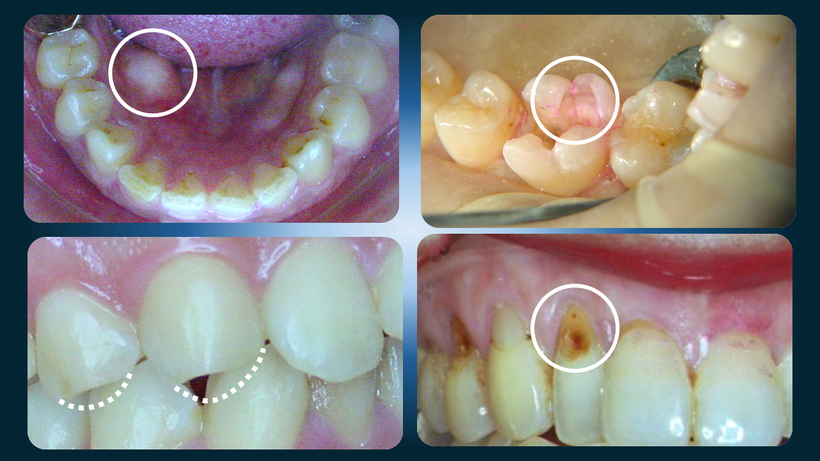

顎関節症で現れる歯の症状、歯のヒビ、下顎骨隆起、切端の咬耗、WSD(楔状欠損)

1.顎の骨の隆起

2.歯に入った大きなヒビ

3.歯の磨耗や先端の欠け

4.根元のえぐれ(WSD、abfraction)

5.歯が異常にしみる,etc.